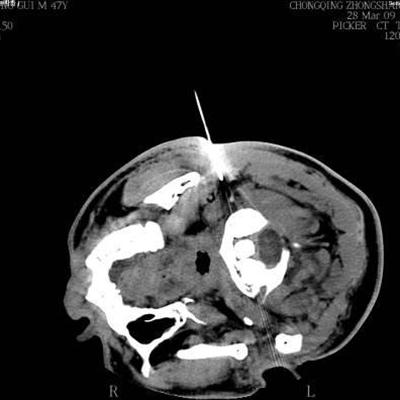

My rhinitis is how many years old problem, I now feel pain in the nasal cavity, and my head also began to pain more and more serious, every night sleep stuffy, breathless, sleep also can't sleep well, see the doctor said is nasopharyngeal carcinoma, for nasopharyngeal cancer can eat chicken? Do you know anything about this? So let's talk about nasopharyngeal cancer can eat chicken.